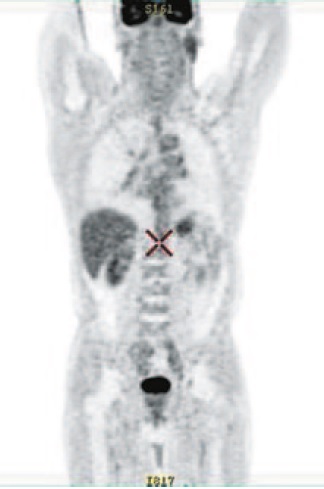

Проведены позитронно-эмиссионная томография (ПЭТ)/КТ для оценки распространенности заболевания (рис. 4). По данным ПЭТ/КТ в верхнем и среднем средостении – метаболически активный конгломерат без четких контуров до 87×76×112 мм; сливается с активными внутригрудными лимфоузлами (максимальный стандартизированный уровень захвата фармпрепарата – SUVmax 7,9).

Рис. 4. ПЭТ/КТ до начала терапии (03.11.2019): а – в прямой, б – в боковой проекции.

Fig. 4. PET/CT before the start of therapy (03.11.2019): a – in the frontal projection, b – in the lateral projection.

С учетом морфологии, данных КТ, магнитно-резонансной томографии и ПЭТ/КТ установлен диагноз: С34.1. Центральный рак правого легкого стадии IV, группы II. T4N3M1. Метастазы в легкое, внутригрудные лимфоузлы.